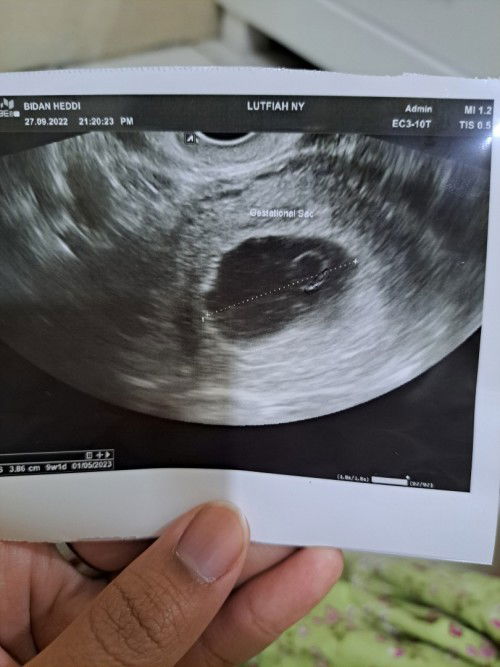

Hamil kosong usia 9week

Bun, mau tanya.. ada ga yg pernah di vonis hamil kosong di usia 9week.. terus harus bagaimana ya bun? Sedih bangett 😭 bingung mesti bagaimana #seriusnanya #hamilkosong #bantusharing #ingintahu #firstmom #pleasehelp #firstbaby #hamilBO

Bun, ada yg pernah di vonis hamil kosong di usia 9week ga bun? Harus gmn ya bun?

Hamil kosong #seriusnanya #bantusharing #ingintahu #pleasehelp